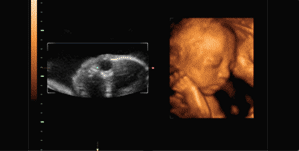

很多孕妈咪都听说过四维彩超,这是产检中重要的一项孕期检查项目,但是,做四维彩超能不能排除唐氏儿呢?估计就是很多怀孕中的孕妈妈关注的问题了。针对这个问题,泉州福兴妇产医院的医生做出了详细介绍。>>>看文章太累,点击在线一对一交流

福兴妇产医院表示,唐氏筛查和四维彩超虽然都可以检查胎儿是否发育正常,但是是两种不同的检查概念,四维彩超是检查胎儿发育状况及外形畸形,唐氏筛查是验血检查胎儿患有唐氏遗传疾病的风险值。四维彩超不能替代唐氏筛查,四维彩超不能排除唐氏儿的出生。

四维彩超检查作用